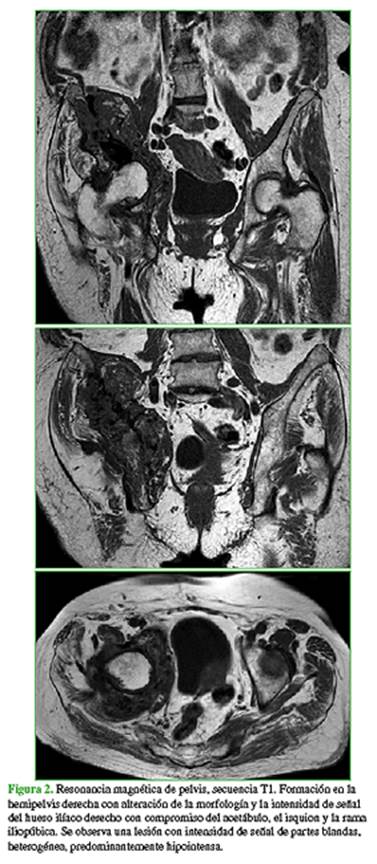

La paciente acudió a nuestra institución en marzo de 2018. En el examen físico, se observó una tumoración palpable en la cara externa del hueso ilíaco derecho asociada a dolor en la cara anterior del muslo homolateral. Refería dolor durante la flexo-extensión de la cadera derecha y a las rotaciones, como así también dolor a la carga sobre ese miembro. Deambulaba únicamente dentro del domicilio asistida con andador. Una radiografía de pelvis (Figura 1) mostró una alteración de la estructura compatible con lesión expansiva que comprometía el hueso ilíaco derecho, de aspecto heterogéneo y bordes irregulares, además de la presencia de cemento producto de la cementoplastia previa.

En la resonancia magnética (Figura 2), se observó una formación en la hemipelvis derecha con alteración de la morfología e intensidad de señal del hueso ilíaco derecho con compromiso del acetábulo, el isquion y la rama iliopúbica; en su topografía, se registró una lesión con intensidad de señal de partes blandas, heterogénea, predominantemente hipointensa en secuencia T1.